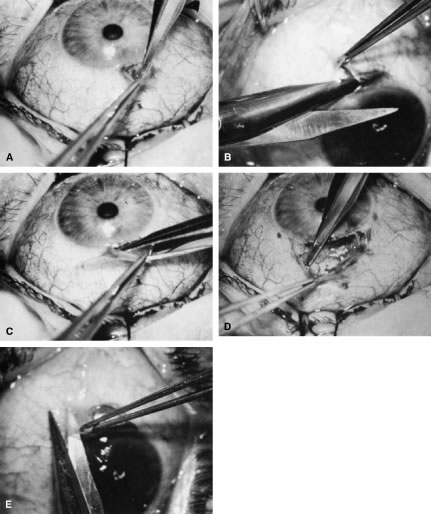

If the decision has been made to perform surgery, the surgeon must consider how to perform the surgery to achieve the desired target pressure range (see Table 14). Although it is not always possible to achieve the desired target pressure range, certain procedures and approaches to surgery give the surgeon the ability to approximate the goal. A guarded filtration procedure performed essentially as described by Watson, for example, in a white patient without risk factors for failure usually will result in IOP of approximately 17 mm Hg, ranging from 15 to 19 mm Hg.26 In contrast, a full-thickness filtering procedure, such as a corneoscleral trephine, usually will result in a mean IOP of approximately 14 mm Hg, with a range of 12 to 16 mm Hg.26

To obtain increasingly lower IOP, it is necessary to modify surgical technique (Table 15). By performing guarded filtration procedures so that the sutures can be released postoperatively, with the use of either laserable or releasable sutures, a lower final IOP can be obtained in some cases. This technique allows a bleb to develop that is similar to that seen in a full-thickness filtration procedure. Such blebs tend to be thin, polycystic, and located directly at the limbus, in contrast to those seen after classic trabeculectomy, which are thicker, lower, more diffuse, and more posterior. When antifibrosis agents (antimetabolites and corticosteroids) are added to procedures designed to develop full-thickness filtration, IOP tends to be sharply reduced.27–29 The blebs associated with the use of 5-fluorouracil (5-FU) and mitomycin are an exaggeration of the full-thickness type of bleb: Often, they are extensive, sometimes involving 360 degrees of the anterior surface of the globe, and the conjunctiva tends to be thin and completely ischemic.30–34

Table 15. Methods Thought to Help Achieve Lower Final Intraocular Pressure After Filtration Procedure

Antimetabolites

Topical corticosteroids (up to equivalent of prednisolone 1% 4 times daily)

Minimal overlap of scleral flap (minimal guarding)

Nasally placed bleb

Use of releasable or laserable sutures in scleral flap

Thin scleral flap

The thin filtration blebs associated with the use of mitomycin or 5-FU may rupture spontaneously. They tend to be so high that the adjacent cornea becomes dry, with the development of an uncomfortable delle. Ptosis tends to develop, and patients often are photophobia One of the most serious concerns is the high incidence of endophthalmitis in patients with thin blebs. When full-thickness blebs were the routine type of glaucoma procedure, endophthalmitis would develop in approximately 1% of patients. When 5-FU was used to develop filtration blebs inferiorly, an 8% rate of endophthalmitis was reported.35–42 Hypotony, even in the absence of a thin bleb, introduces serious problems. The soft eye does not maintain a constant optical state, and it has a constantly changing amount of astigmatism that makes it impossible to correct. Each time the patient blinks, the amount of astigmatism changes. Macular and disc edema cause reduced central acuity and deterioration of the visual field, and the globe may have a constant, visceral ache. Patients with such eyes are not comfortable.